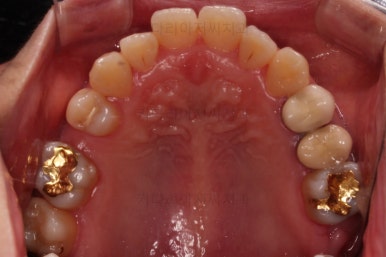

부산연산동치과 초진 시 파노라마 X-ray 사진입니다.

화살표 부분이 결손치아 부분입니다.

우측의 화살표 부분은 임플란트를 하면 되는데, 좌측의 화살표 부분은 임플란트를 못합니다.

뒤쪽 어금니들이 앞으로 쓰러져서 그런데요.

그렇다고 그냥 두면 뒷치아들은 더 기울어져 쓰러지게 돼요.

쓰러진 치아는 씹는 힘이 제대로 전달되지 못해 치아 수명이 굉장히 짧아지게 됩니다.